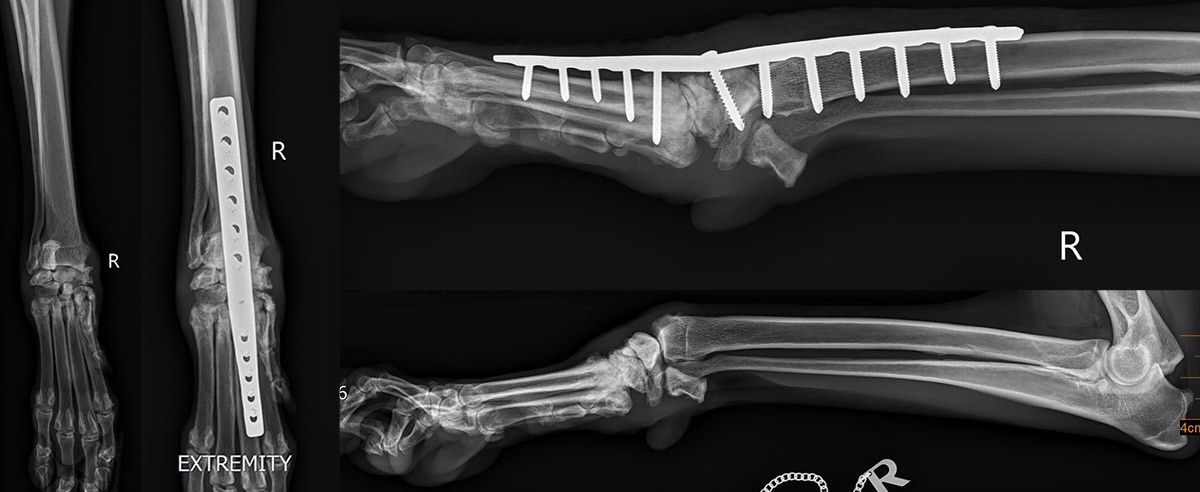

- Bildgebende Verfahren

• Röntgenaufnahmen